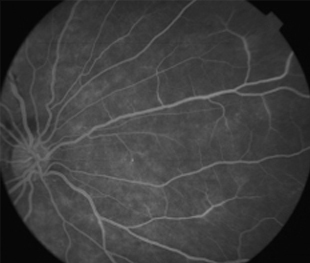

Angiografía OD